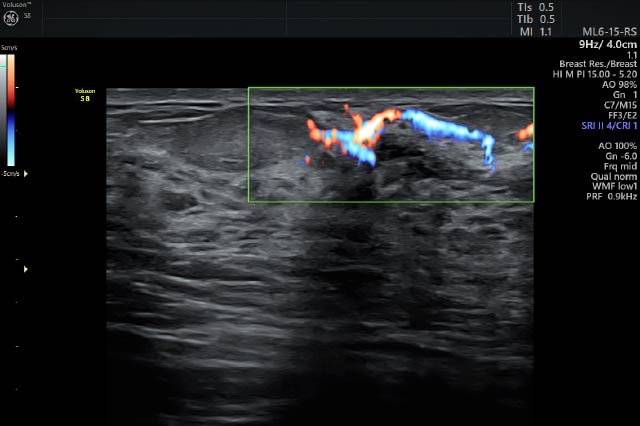

マンモグラフィで異常を指摘された方や乳房に違和感やしこりを感じる方の精密検査を行います。エラストグラフィと呼ばれるしこりの硬さを判定する検査や穿刺吸引細胞診に対応しています。